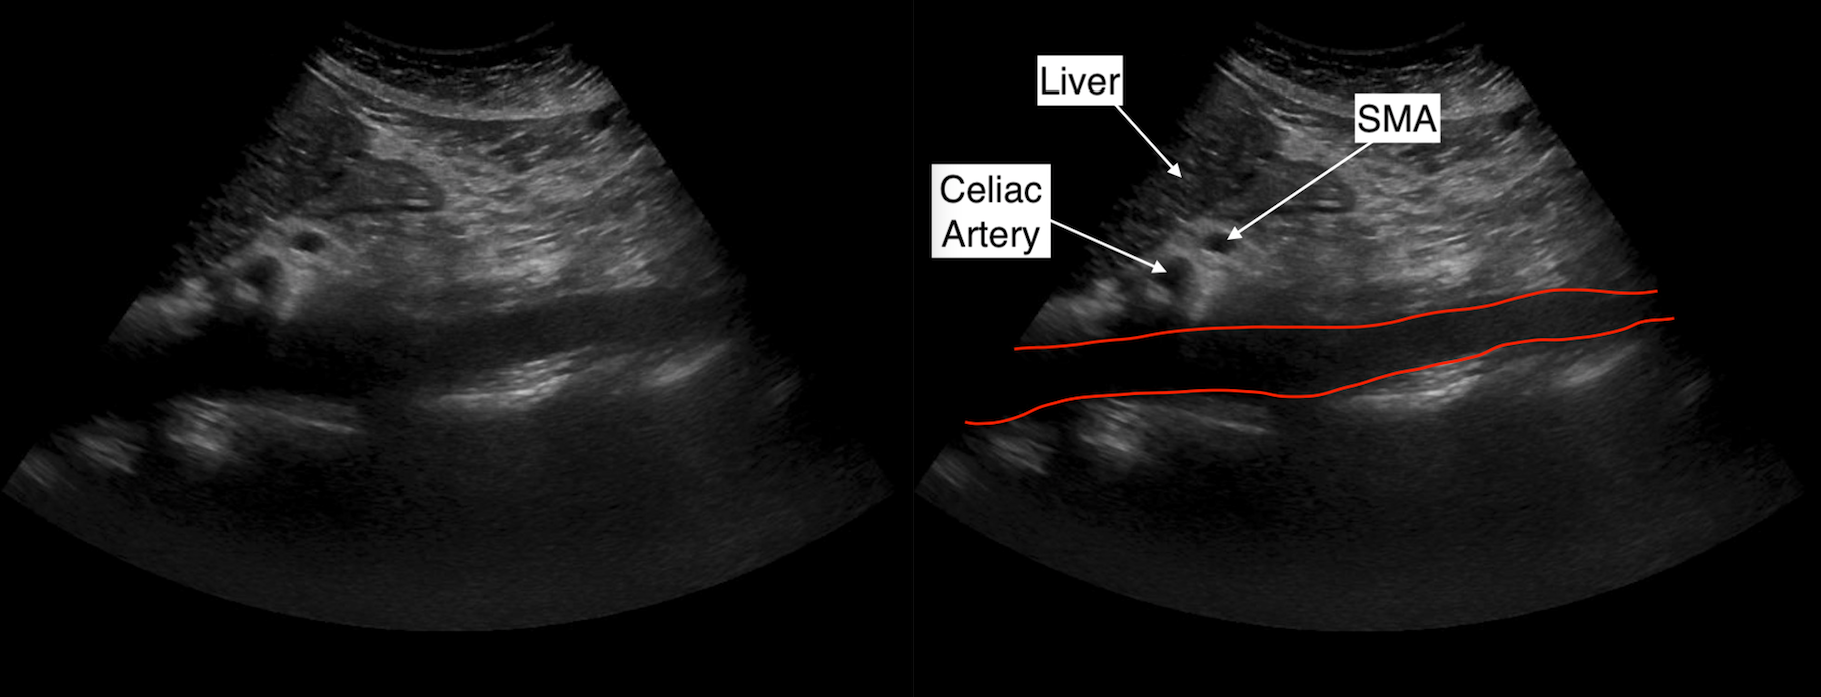

Ultrasonido abdominal en el que se aprecia dilatación del conducto

Source: www.researchgate.net